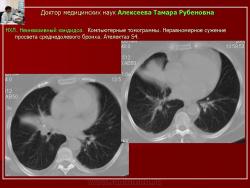

Рис. 10. Б-ной А. НХЛ. Неинвазивный кандидоз.

Обзорные рентгенограммы. Ателектаз средней доли.

Рис. 11. Тот же б-ной А. НХЛ. Неинвазивный кандидоз.

Компьютерные томограммы. Неравномерное сужение просвета среднедолевого бронха. Ателектаз S4.

Неинвазивная форма бронхолегочного кандидоза, установленная у 4-х больных, характеризовалась ростом грибов в распадающейся первичной опухоли (рис.9) и в просвете бронха (рис. 10, 11), что сопровождалось нарушением вентиляции в дистальнее расположенном участке легкого.